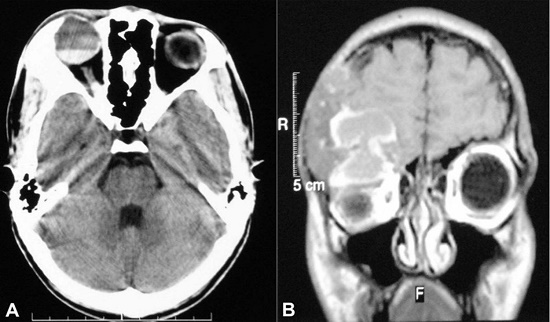

A 16-year-old male presented with a history of headache and swelling over the right supraorbital region of 25 days’ duration. There was no history of diplopia, nystagmus, or blurred vision. On examination, there was a fixed, non-tender, hard, bony bulge present over the right supraorbital region.

Computed tomography showed a bony expansion and the presence of multiloculated cystic swelling in the orbital part of the right frontal bone, suggestive of an aneurysmal bone cyst (Figures 3A and 3B). With the working diagnosis of a right supra-orbital aneurysmal bone cyst, a right fronto temporoparietal craniotomy with right orbital roof and lateral wall removal were performed.

Sections examined from the excised part of the frontal bone showed a normal cortical bone at the periphery, while a lesional tissue was identified in the center (Figure 4A). This center lesion revealed numerous irregular-shaped trabeculae of immature woven bone without osteoblastic rimming (Figures 4B and 4C). Large areas of cystic degeneration were also identified (Figure 4D).

There were no features to suggest an aneurysmal bone cyst, such as blood-filled cystic spaces separated by a spindle cell and multinucleated giant cells.

Based on the histomorphological features, diagnosis of fibrous dysplasia with secondary cystic change was made. Postoperatively, the patient presented a cosmetic improvement and has been symptom-free for the year following surgery.